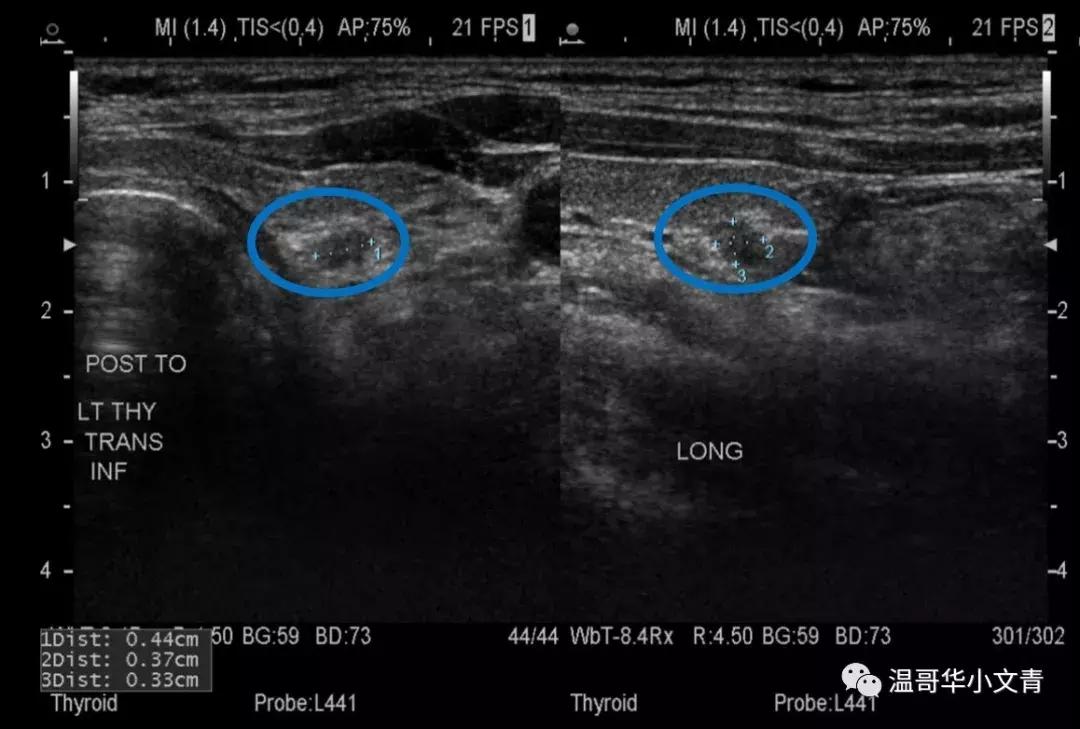

第四个图是一个术前发现的气管旁甲状腺后方可疑淋巴结,淋巴结长径是4毫米。这个淋巴结也是比较圆,边界不规则,比较可疑,术后病理显示这个淋巴结里的转移灶是3毫米。